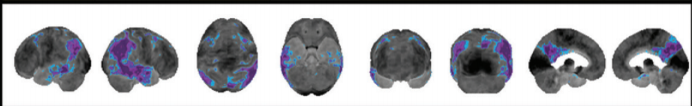

Alzheimer disease